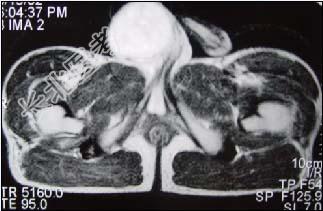

- 单项选择题29岁男性患者,右侧睾丸肿痛5个多月, 行MRI检查,如图所示, T1加权见右侧阴囊内见球形肿块,呈中等信号, 其内信号不均,T2加权肿块为高信号, 最可能的结果是 ( )